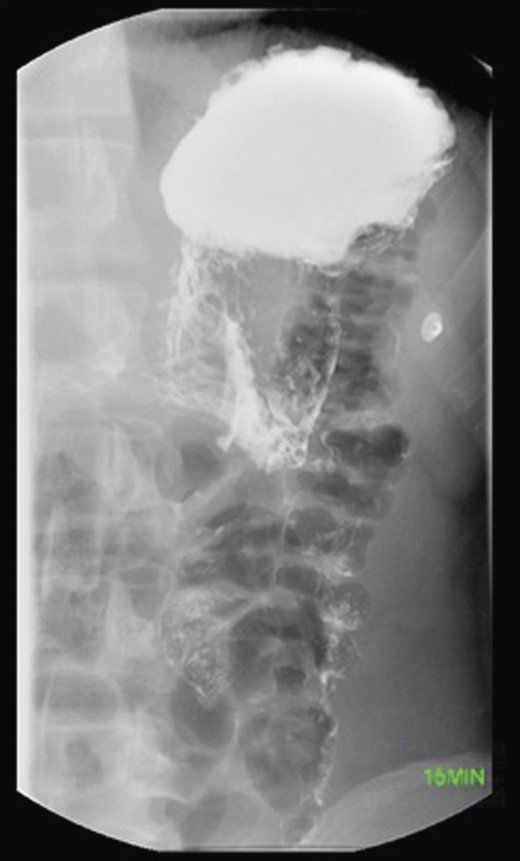

The laboratory results of the patient were creatinine 1.10 mg/dl (0.60–1.00), serum glucose 124 mg/dl (65–100), hemoglobin 16.9 µl (12.0–16.0) and total bilirubin 1.6 mg/dl (0.2–1.0). A gastroenterologist was consulted and an urgent EGD was done, showing negative insufflations of the stomach that were characteristic of a volvulus. The diagnosis of mesenteroaxial volvulus was confirmed by single contrast upper GI (UGI) imaging (Fig. 1).

The patient underwent a laparoscopic gastrostomy-tube gastropexy. A 10 mm laparoscope and three 5 mm ports were placed. There was no evidence of a hiatal hernia, diaphragmatic hernia or Meckel's diverticulum on visualization. The patient had healed well from his previous appendectomy. A crease on the stomach was visible where the volvulus had occurred. A 24-French gastrostomy tube was inserted percutaneously into the stomach and inflated. Using the gastrostomy tube, the stomach was approximated to the posterior aspect of the anterior abdominal wall. A point along the greater curve of the stomach, distal to the volvulus, was chosen to suture the stomach to the abdominal wall with permanent sutures. The patient tolerated the surgical procedure well (Fig. 2) and was discharged 4 days later.

Diagnosis is made with clinical suspicion and imaging. X-ray, EGD, CT scan and upper GI contrast study all can be used to visualize a volvulus. An X-ray often shows a retrocardiac air bubble or an expanded air fluid level in the chest, while an upper GI contrast study may reveal an ‘upside-down’ stomach where the pylorus is positioned above the fundus [1, 4, 5]. The preferred treatment for gastric volvulus is repair of the paraesophageal hernia with fundoplication with or without gastropexy. In the absence of diaphragmatic pathology, the preferred treatment is anterior gastropexy whereby the stomach is sutured to the anterior abdominal wall. A tube gastrostomy can be used to further secure the stomach. The procedure can be done either open or laparoscopically. In severe cases where ischemic injury has caused necrosis, gastrectomy may be required [2].